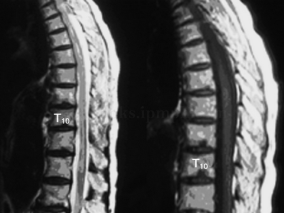

1小时条评论相关链接: 68岁女性,因主动脉夹层接受介入治疗。谁知术后第2天,患者自觉胸痛好转,可下床活动后,夜间突然出现双下肢剧烈疼痛。予输血浆、抗感染、改善循环及甲泼尼龙等治疗,患者病情无明显变化。是何原因让患者旧疾刚治,又添新愁? 脊髓前动脉综合征(anter...